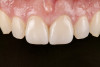

Figure 1 through Figure 14 illustrate steps involved in the fabrication of zirconia restorations using CEREC. Figure 15 through Figure 21 show preparations and postoperative results in two case examples of patients who received zirconia indirect restorations.